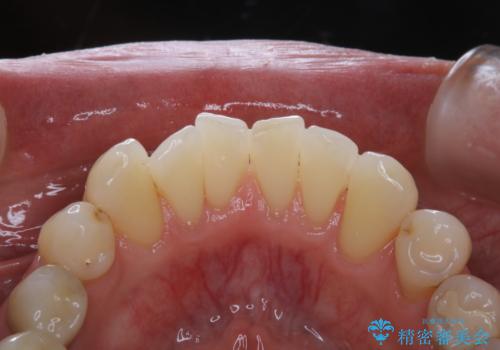

- PMTCでのメンテナンスを定期的に行っている方です。PMTC30分コースを行いました。

日々の磨き残しなどをそのまま放置すると、細菌が固まり硬い歯石になります。

歯石になってしまうと、とても硬く、歯ブラシで取り除くことが出来なくなります。

よって、歯科衛生士による専門的なクリーニングを定期的に行うことがとても大切です。

メンテナンスの間隔は個人差がありますが、基本的には2~3カ月に一度行うことをおすすめしています。